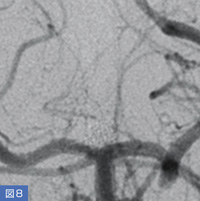

72歳、女性。未破裂脳底動脈先端部動脈瘤(図6)に対して瘤内塞栓術を行った。3D-DAで穿通枝の分岐部を確認し(図7)、塞栓術中も穿通枝の状態を確認しながら塞栓を進め、良好な塞栓を得ることができた(図8)。

図7 図6の症例の3D-DA像

図6の症例の3D-DA像